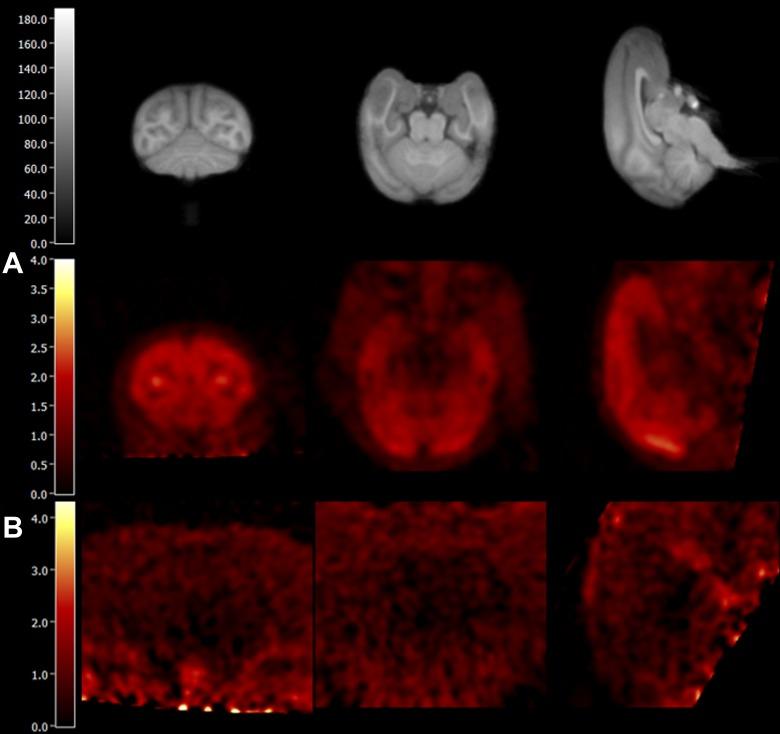

The myriad physiological functions of γ-amino butyric acid (GABA) are mediated by the GABA-benzodiazepine receptor complex comprising of the GABA, GABA, and GABA groups. The various GABA subunits with region-specific distributions in the brain subserve different functional and physiological roles. For example, the sedative and anticonvulsive effects of classical benzodiazepines are attributed to the α subunit, and the α and α subunits mediate the anxiolytic effect. To optimize pharmacotherapies with improved efficacy and devoid of undesirable side effects for the treatment of anxiety disorders, subtype-selective imaging radiotracers are required to assess target engagement at GABA sites and determine the dose-receptor occupancy relationships. The goal of this work was to characterize, in nonhuman primates, the in vivo binding profile of a novel positron emission tomography (PET) radiotracer, [C]ADO, which has been indicated to have functional selectivity for the GABA α/α subunits. High specific activity [C]ADO was administrated to 3 rhesus monkeys, and PET scans of 120-minute duration were performed on the Focus-220 scanner. In the blood, [C]ADO metabolized at a fairly rapid rate, with ∼36% of the parent tracer remaining at 30 minutes postinjection. Uptake levels of [C]ADO in the brain were high (peak standardized uptake value of ∼3.0) and consistent with GABA distribution, with highest activity levels in cortical areas, intermediate levels in cerebellum and thalamus, and lowest uptake in striatal regions and amygdala. Tissue kinetics was fast, with peak uptake in all brain regions within 20 minutes of tracer injection. The one-tissue compartment model provided good fits to regional time-activity curves and reliable measurement of kinetic parameters. The absolute test-retest variability of regional distribution volumes ( V) was low, ranging from 4.5% to 8.7%. Pretreatment with flumazenil (a subtype nonselective ligand, 0.2 mg/kg, intravenous [IV], n = 1), Ro15-4513 (an α-selective ligand, 0.03 mg/kg, IV, n = 2), and zolpidem (an α-selective ligand, 1.7 mg/kg, IV, n = 1) led to blockade of [C]ADO binding by 96.5%, 52.5%, and 76.5%, respectively, indicating the in vivo binding specificity of the radiotracer. Using the nondisplaceable volume of distribution ( V) determined from the blocking studies, specific binding signals, as measured by values of regional binding potential ( BP), ranged from 0.6 to 4.4, which are comparable to those of [C]flumazenil. In conclusion, [C]ADO was demonstrated to be a specific radiotracer for the GABA receptors with several favorable properties: high brain uptake, fast tissue kinetics, and high levels of specific binding in nonhuman primates. However, subtype selectivity in vivo is not obvious for the radiotracer, and thus, the search for subtype-selective GABA radiotracers continues.

γ-氨基丁酸(GABA)的众多生理功能是由GABA-苯二氮䓬受体复合物介导的,该复合物由GABA、GABA和GABA组构成。大脑中具有区域特异性分布的各种GABA亚基发挥着不同的功能和生理作用。例如,经典苯二氮䓬类药物的镇静和抗惊厥作用归因于α亚基,而α和α亚基介导抗焦虑作用。为了优化药物治疗,提高治疗焦虑症的疗效并避免不良副作用,需要亚型选择性成像放射性示踪剂来评估GABA位点的靶点结合情况,并确定剂量-受体占有率关系。这项工作的目标是在非人灵长类动物中表征一种新型正电子发射断层扫描(PET)放射性示踪剂[C]ADO的体内结合谱,该示踪剂已被证明对GABAα/α亚基具有功能选择性。向3只恒河猴注射高比活度的[C]ADO,并在Focus-220扫描仪上进行120分钟的PET扫描。在血液中,[C]ADO代谢速度相当快,注射后30分钟约36%的母体示踪剂留存。[C]ADO在大脑中的摄取水平很高(峰值标准化摄取值约为3.0),且与GABA分布一致,皮质区域活性水平最高,小脑和丘脑活性水平中等,纹状体区域和杏仁核摄取最低。组织动力学很快,示踪剂注射后20分钟内所有脑区均达到摄取峰值。单组织室模型能很好地拟合区域时间-活性曲线,并可靠地测量动力学参数。区域分布体积(V)的绝对重测变异性很低,范围为4.5%至8.7%。用氟马西尼(一种亚型非选择性配体,0.2mg/kg,静脉注射[IV],n = 1)、Ro-15-4513(一种α选择性配体,0.03mg/kg,静脉注射,n = 2)和唑吡坦(一种α选择性配体,1.7mg/kg,静脉注射,n = 1)预处理分别导致[C]ADO结合被阻断96.5%、52.5%和76.5%,表明该放射性示踪剂的体内结合特异性。根据阻断研究确定的不可置换分布体积(V),通过区域结合电位(BP)值测量的特异性结合信号范围为0.6至4.4,与[C]氟马西尼的相当。总之,[C]ADO被证明是一种针对GABA受体的特异性放射性示踪剂,具有几个有利特性:高脑摄取、快速组织动力学以及在非人灵长类动物中高水平的特异性结合。然而,该放射性示踪剂的体内亚型选择性并不明显,因此,对亚型选择性GABA放射性示踪剂的探索仍在继续。